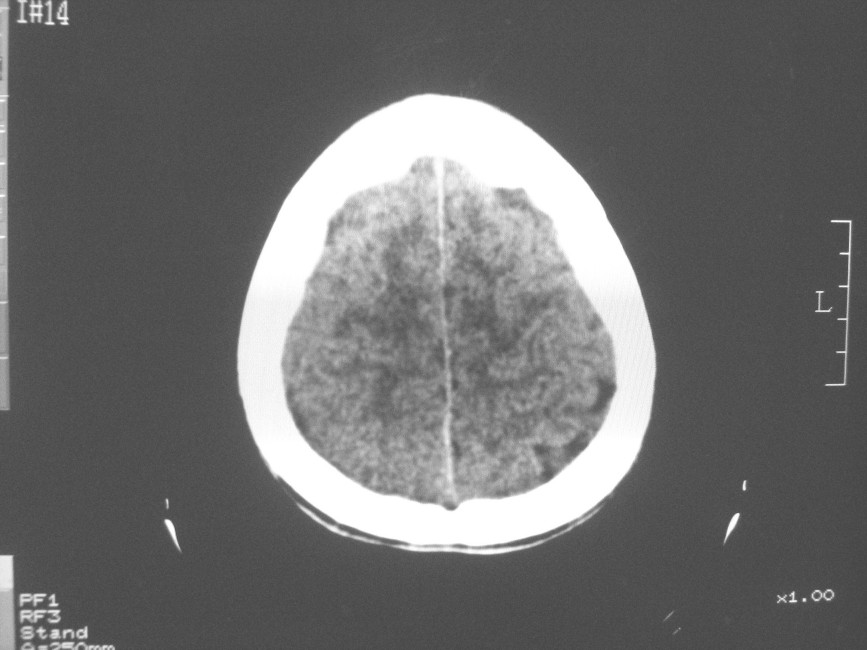

以下是引用zzyy在2008-6-16 10:13:00的发言:[br]两侧脑白质呈对称性密度减低,病儿有发热及脑膜刺激征。考虑急性病毒性脑炎。